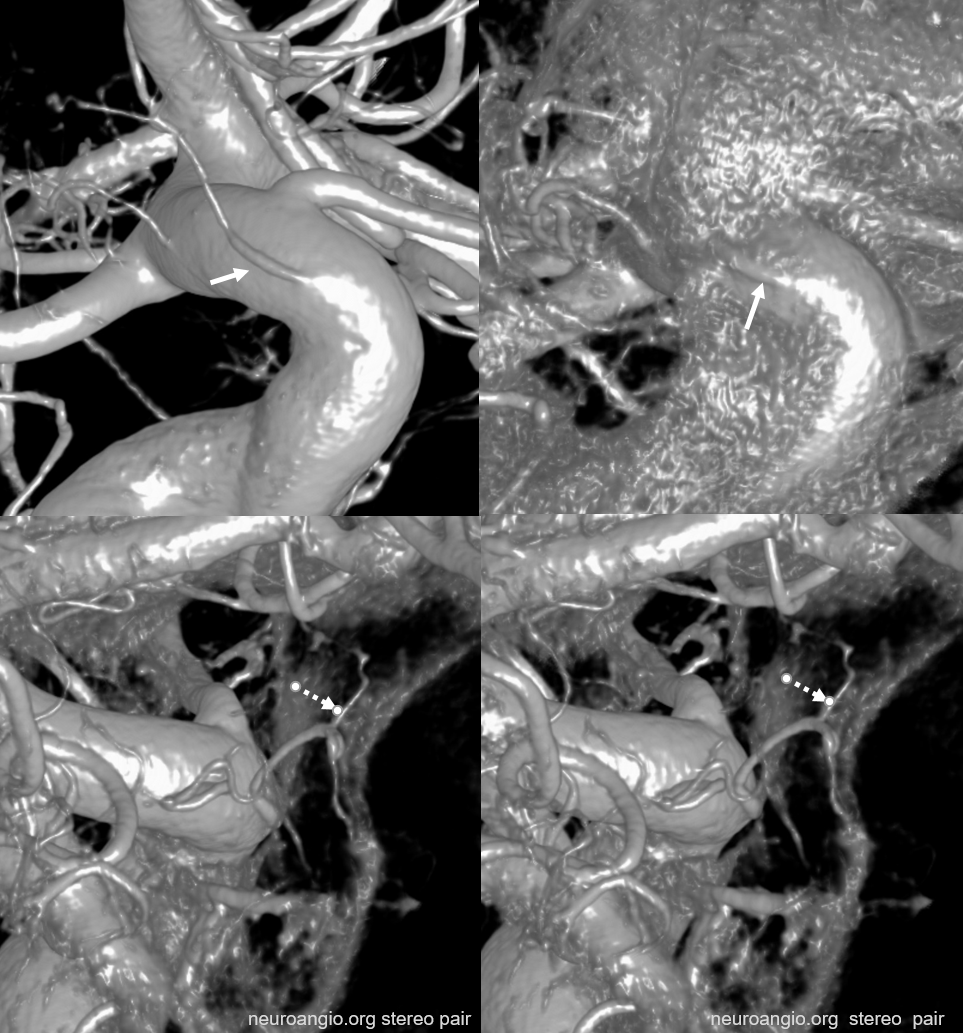

Posterior Pituitary Supply — MHT Balance

Excellent example of contralateral balance. On the left, there is a hypoplastic posterior hypophyseal network (part of MHT, arrowhead), and a prominent superior hypophyseal artery (associated with a small aneurysm). On the right, the opposite is true — large inferior hypophyseal arteries (dashed arrows) extending past midline due to contralateral hypoplasia, and a smaller superior hypophyseal, without aneurysm — not visible on these VRs, but seen on subsequent MIP images

MIP images — there is a small right superior hypophyseal artery present

Another example

Spectrum and balance again. Usually, the inferior hypophyseal branches from the MHT supply the posterior pituitary. Here, the MHT is well-developed, but primarily supplies the free margin of the tentorium, while the posterior pituitary is fed by the superior hypophyseal branch (arrow).

Same case MHT — the larger trunk (dashed arrow) is mainly marginal tentorial, smaller one (arrowheads) is clival branches inferiorly towards anastomoses with ascending pharyngeal counterparts

Same case MHT — the larger trunk (dashed arrow) is mainly marginal tentorial, smaller one (arrowheads) is clival branches inferiorly towards anastomoses with ascending pharyngeal counterparts

Yet another one — large anterior branch (with infundibulum), no ipsilateral MHT supply

See smaller “middle” hypophyseal as well